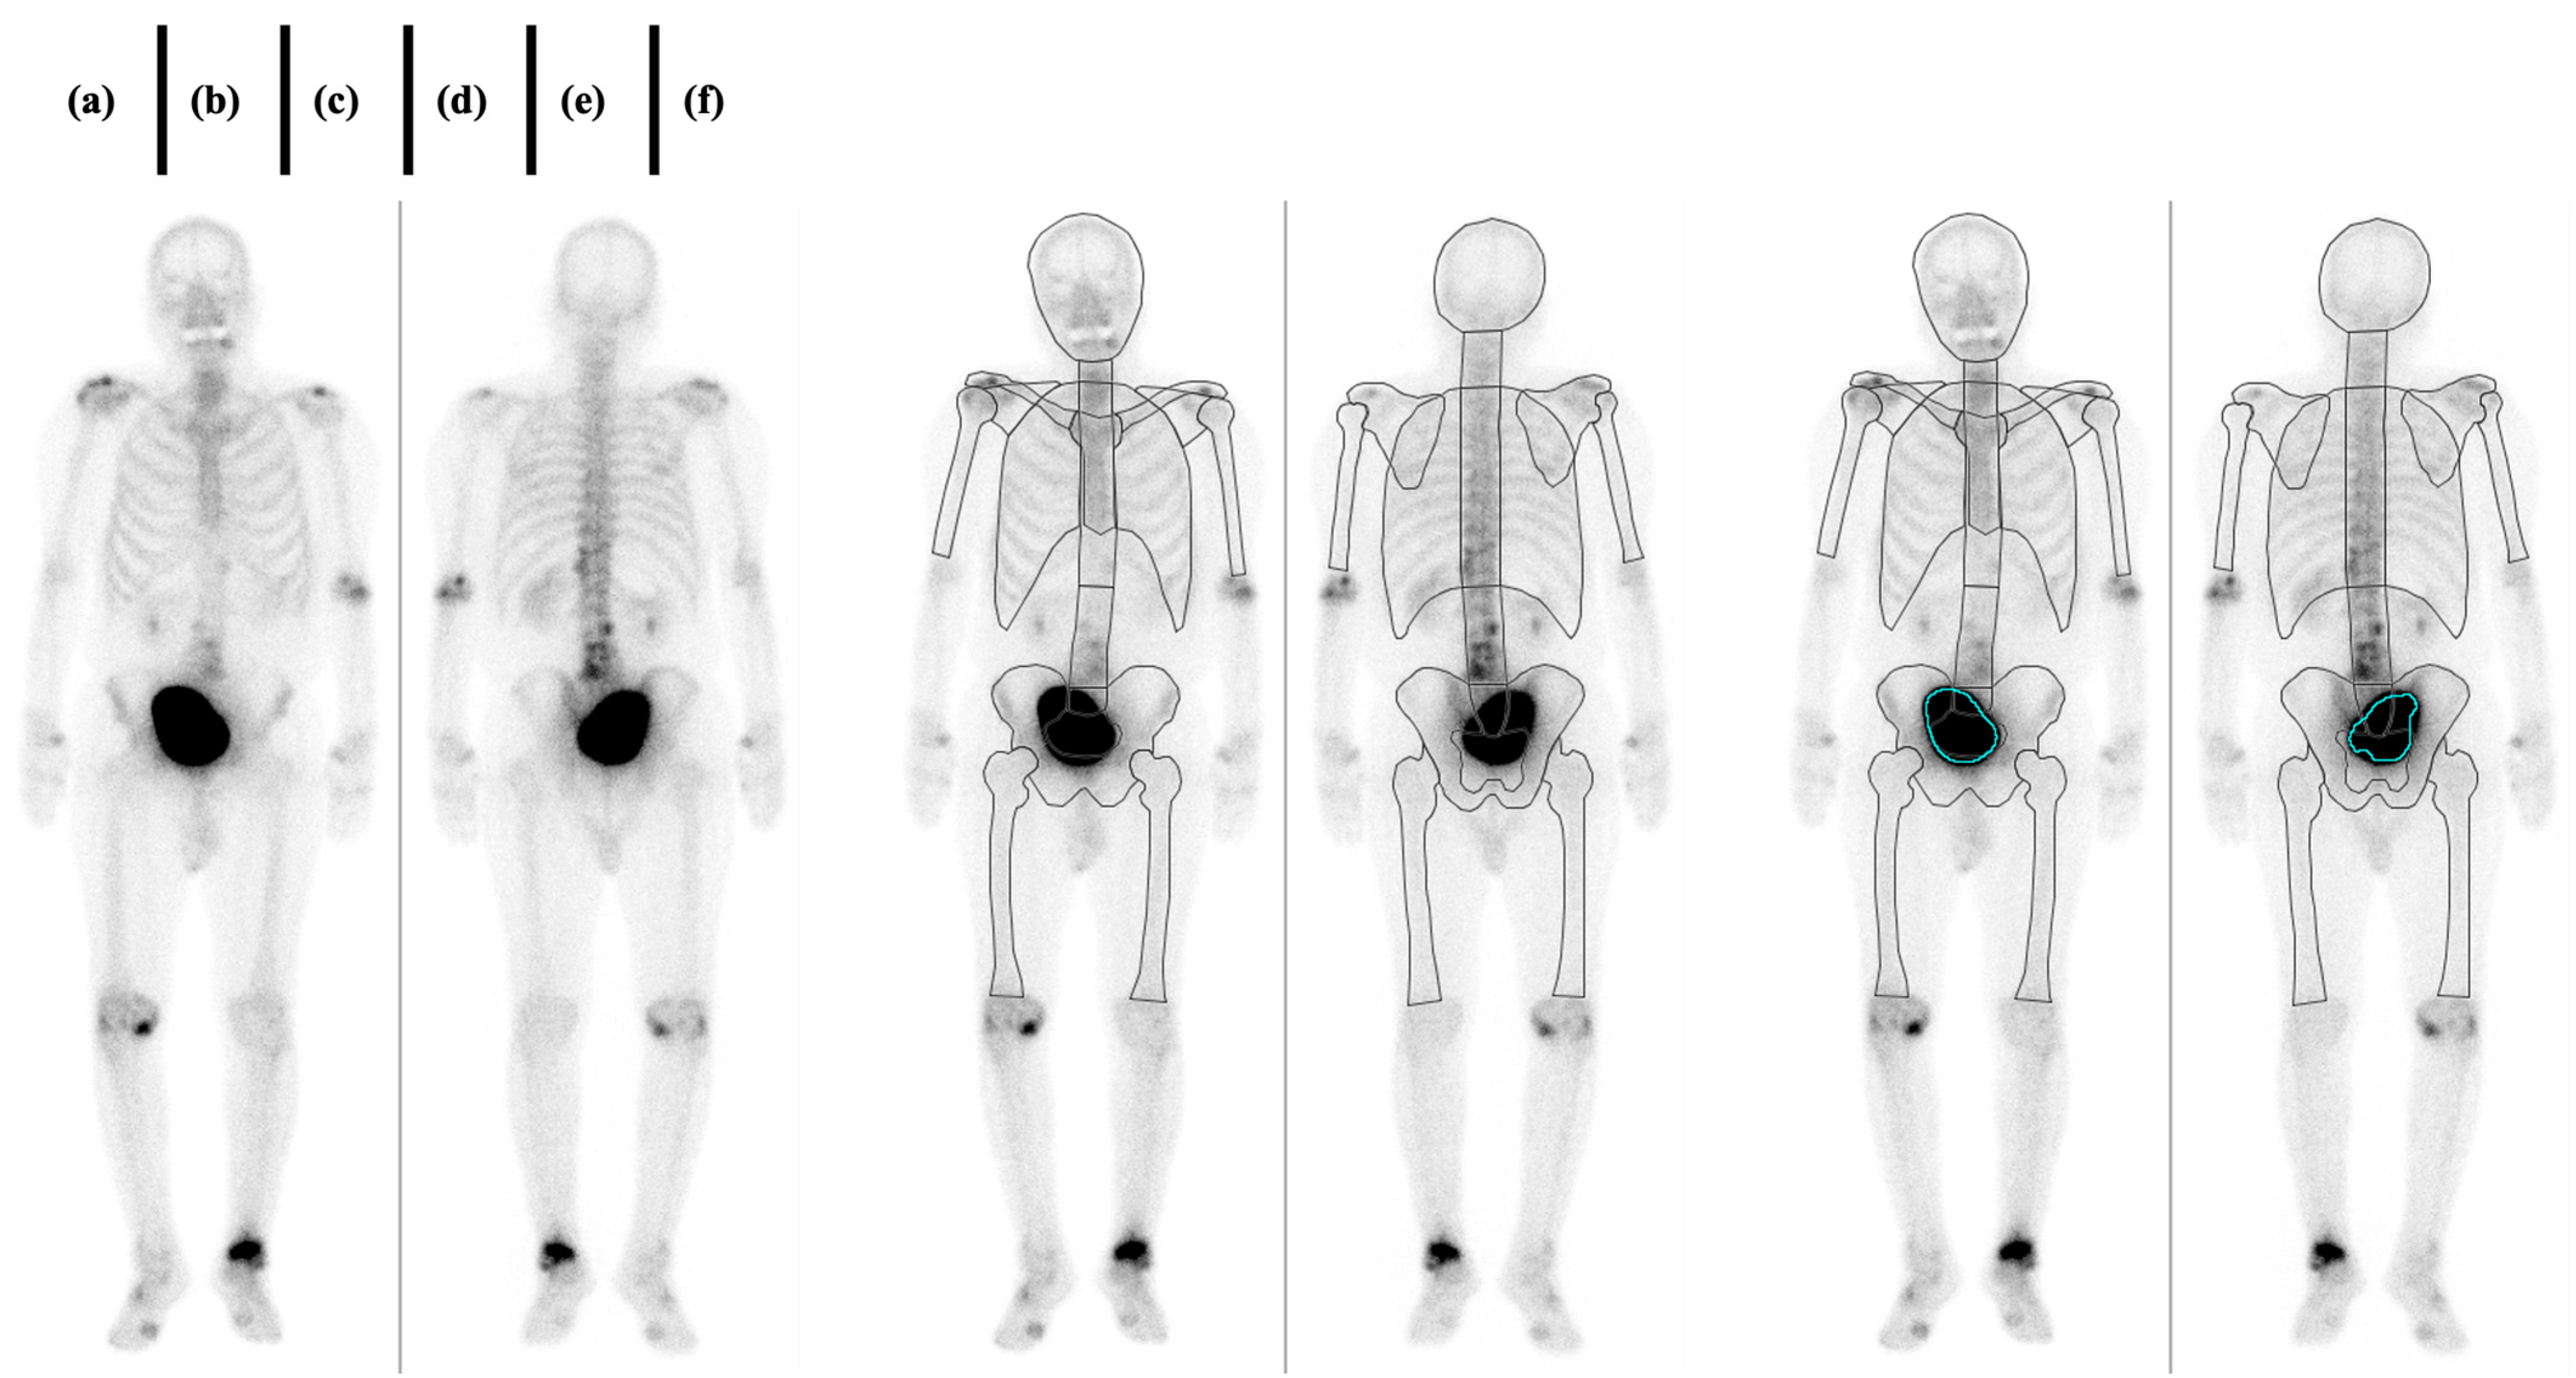

2. Materials and Methods

2.3. Imaging

3. Results